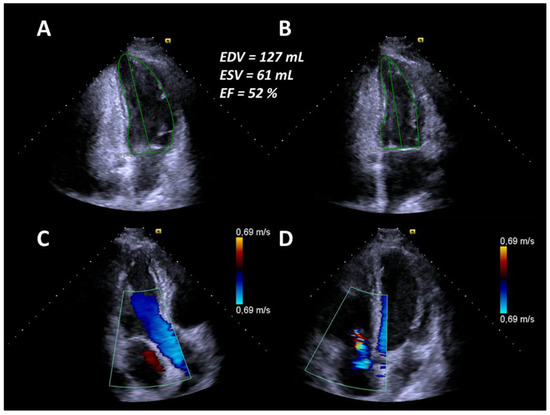

In April 2019, six months after AHSCT, the patient was readmitted due to unusual weakness, fatigue, and newly developed leg edema with a mRSS of 11 points (Figure 1). Laboratory testing revealed elevated NT-proBNP value of 11,189 pg/mL. Echocardiography revealed an LVEF of 32% and pericardial effusion as well as newly developed mitral and tricuspid regurgitation corresponding to acute heart failure (Figure 3).

At the same time, CT changes and spirometric lung function parameters slightly improved. Subsequently, heart failure treatment was intensified with carvedilol, thiazide diuretics, and a higher dose of ACE inhibitors, resulting in concomitant improvement of cardiac parameters. Due to further progression of the disease—despite AHSCT—the patient started on monotherapy with RTX in July 2019. In August 2019, after completion of the first cycle of RTX, clinical symptoms and spirometry parameters ameliorated noticeably (FVC 72.5% predicted, FEV1 79.2% predicted, FEV1/FVC ratio 89.8%), conversely DLCO slightly deteriorated to 38.2% predicted (Figure 1). In October 2019, after completion of the second cycle of rituximab, lung function (FVC 91% predicted, FEV1 95% predicted, FEV1/FVC ratio 84%, DLCO 44% predicted) and mRSS (1 point) further improved significantly (Figure 1). There was also a significant improvement of the echocardiographic findings to a LVEF of 52%, no mitral regurgitation and mild tricuspid regurgitation (Figure 4). Additionally, NT-proBNP levels decreased to 2289 pg/mL.

In the present case, the patient initially responded to the administered immunosuppressive therapy. However, SSc relapsed and rapidly progressed resulting in the involvement of several internal organs. According to the recommendations of the EULAR [8] and a recent study by Henes et al. [9], AHSCT should be considered for the treatment of selected patients with rapid progressive SSc at high risk of organ failure. Therefore, the decision for AHSCT was made. However, only six months after AHSCT, the patient developed symptoms and systemic involvement of progressive SSc with acute heart failure again, which was unexpected as AHSCT is associated with a remission of disease activity lasting up to five years [10]. Additionally, DLCO remained low despite improvement of fibrotic changes in a HRCT scan of the lungs. Restarting RTX, however, finally led to significant improvement of the patient’s symptoms and activity score. Interestingly, heart valve regurgitations were reversible after rituximab treatment, as documented by echocardiography (Figure 4). To the best of our knowledge, this is the first report of heart valve involvement and reversible regurgitation after immunosuppression in SSc. RTX has beneficial effects in SSc patients, while there are no reported data on heart valve involvement. Furthermore, progression of SSc after such a short interval of AHSCT has not yet been reported.

Figure 3. (A) End-diastolic borders of the left ventricle in the apical two-chamber view. (B) End-systolic borders of the left ventricle in the apical two-chamber view. (C) Mild to moderate mitral regurgitation in the apical three-chamber view. (D) Moderate tricuspid regurgitation in the apical four-chamber view.